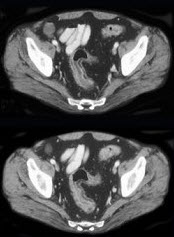

女,30岁,腹胀、腹泻6个月,伴乏力,低热3个月,无盗汗,既往健康。查体:腹平软,右下腹压痛阳性,全腹未触及包块,肠鸣音活跃。 肠镜检查如图,最可能为下列哪种疾病()。

A:血吸虫病

B:溃疡性结肠炎

C:Crohn病

D:阿米巴痢疾

E:细菌性痢疾